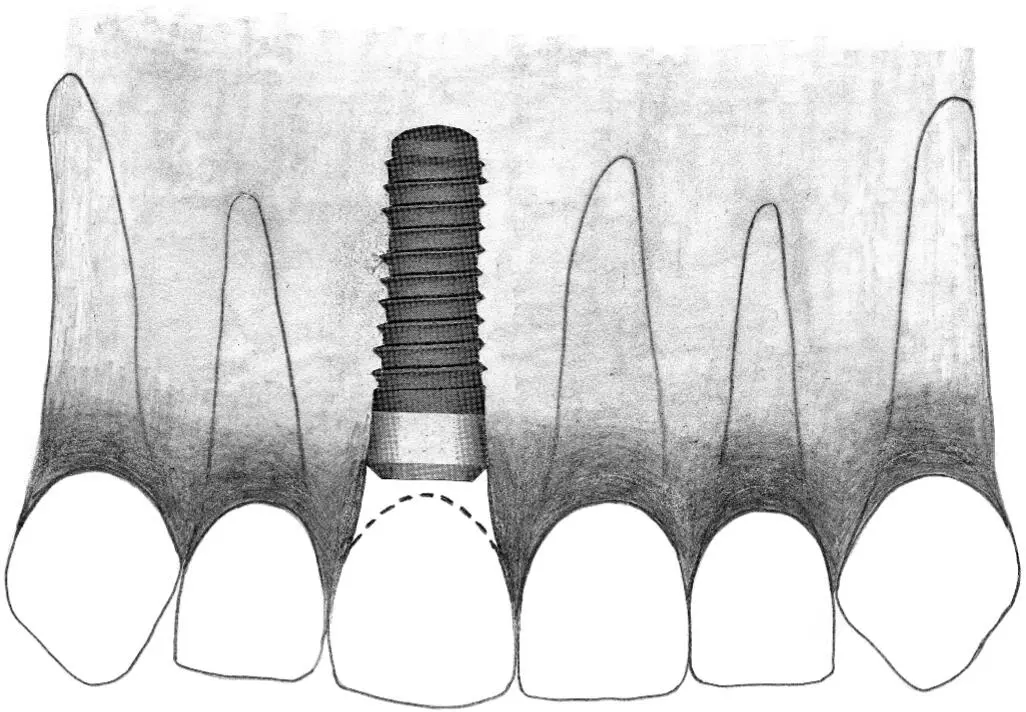

Fig 2-4 Wide neck implant.

Fig 2-4a A wide neck implant is ideal for a single-tooth gap in the first molar position.

Fig 2-4b In a posterior distal extension situation, a standard implant and a wide neck implant are ideal replacements for a missing second premolar and first molar, respectively.